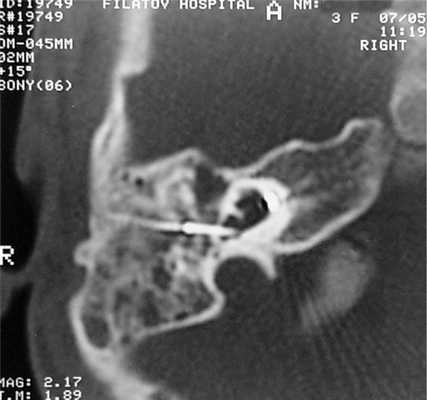

У одного пациента на КТ определялись двусторонняя аномалия внутреннего уха по типу Мондини (рис. 3), двусторонний локальный порок развития цепи слуховых косточек, костная облитерация лабиринта, включая улитку справа. На МРТ внутриулитковая жидкость справа не определялась, слева количество внутриулитковой жидкости было в норме.

Рис. 3. КТ, аксиальная проекция. Аномалия Мондини, состояние после КИ.